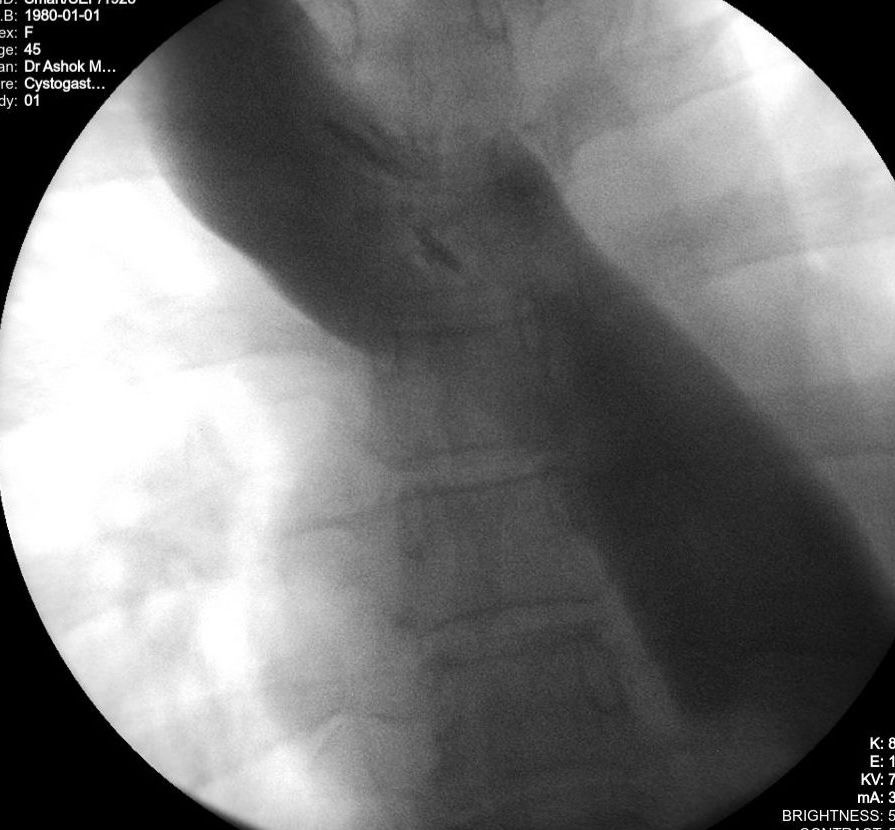

Successful POEM for Achalasia Cardia via Anterior Approach

We are pleaed to announce that last week at GI-One Hospital, we successfully performed a Per Oral Endoscopic Myotomy (POEM) using the Anterior approach in a patient with sigmoid esophagus. The procedure went smoothly, and the patient was discharged on postoperative day 2.

🔹 Anterior POEM: More challenging — multiple vascular indentations and pulsations demand careful preservation of longitudinal muscles during myotomy. Scope manipulation is also trickier, particularly during mucosal closure.